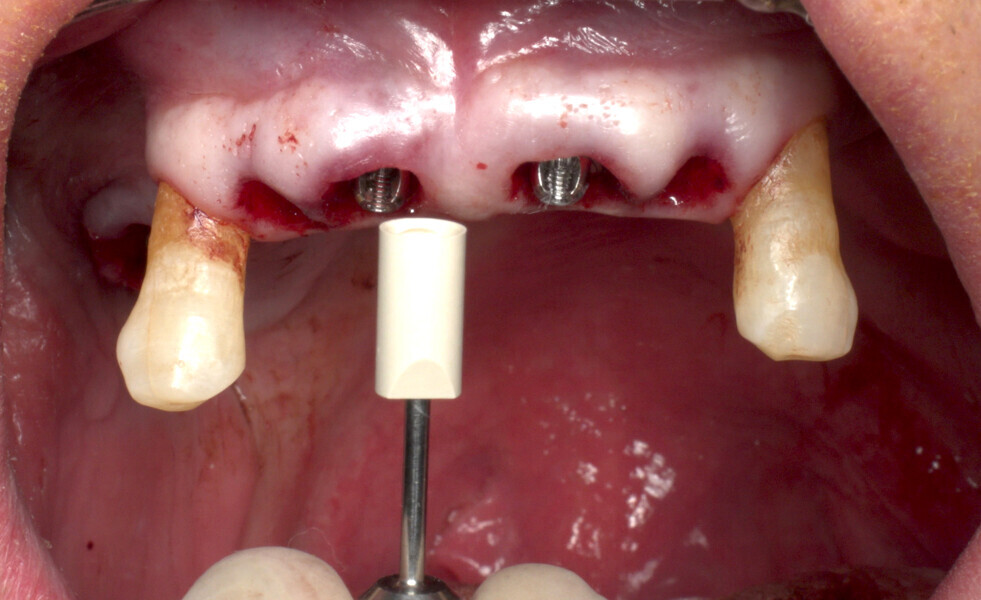

The fully digital Pro Arch protocol